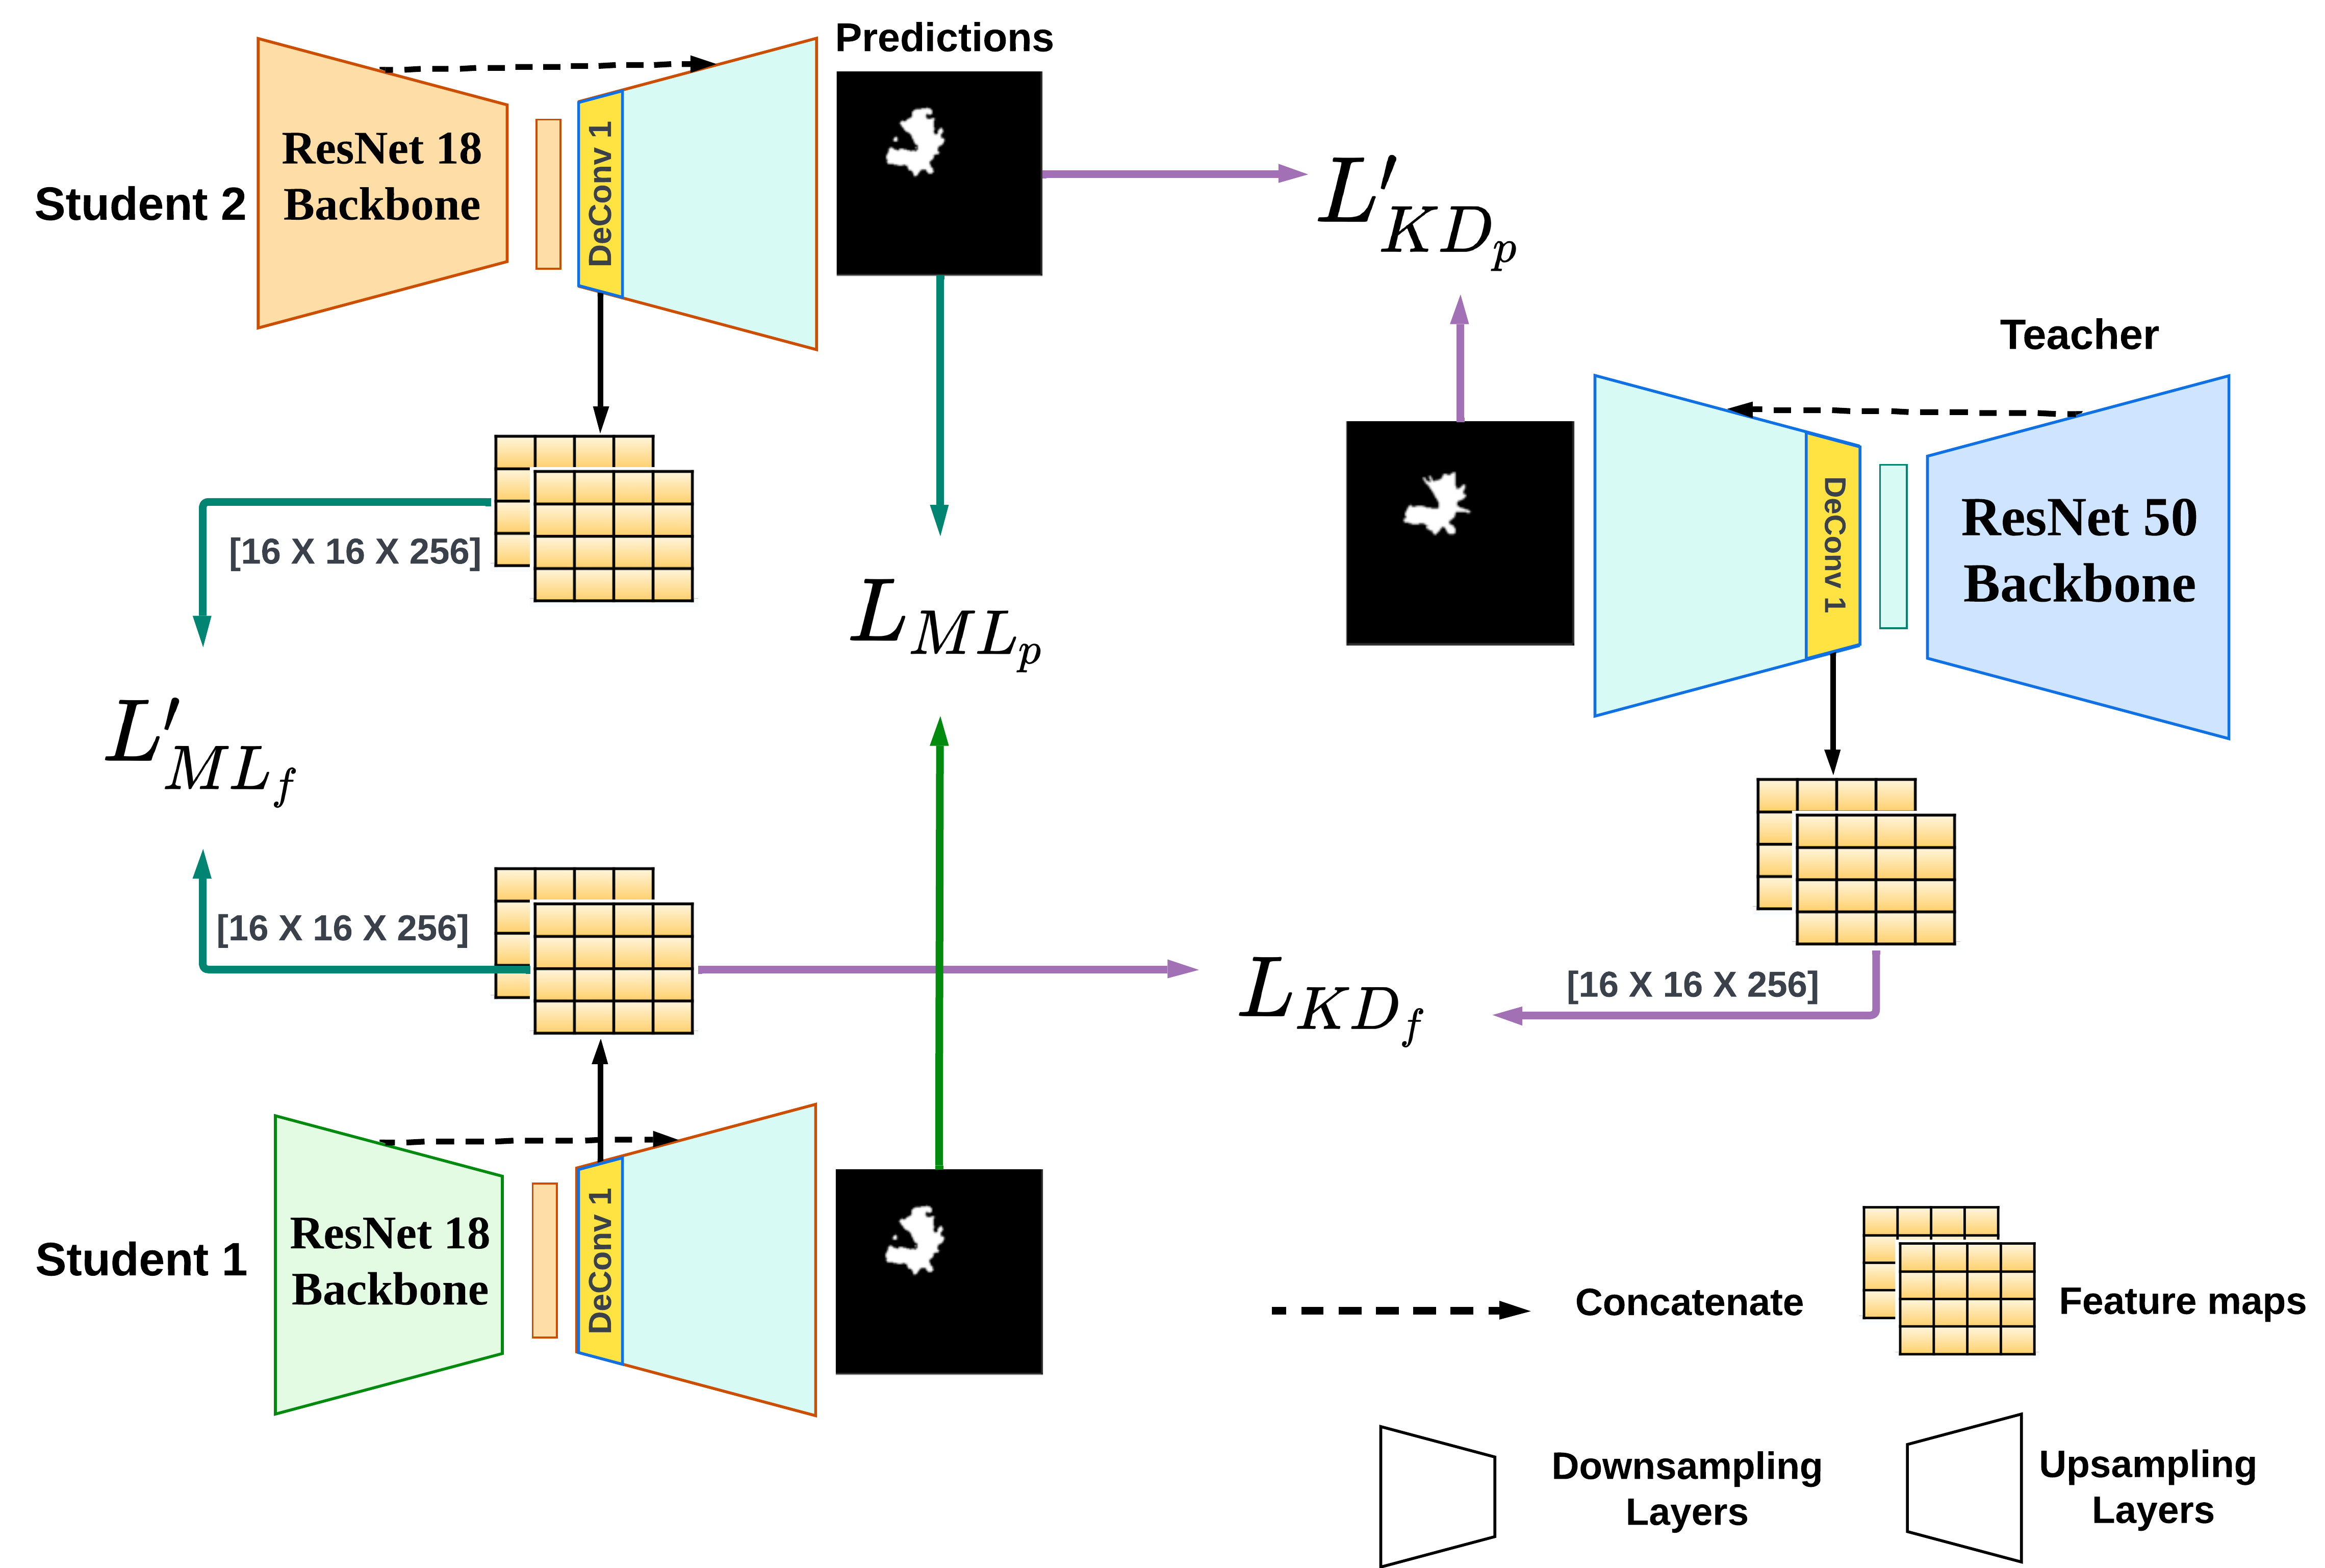

Figures 2 (a) and (b) depict the standard distillation techniques used for knowledge distillation and mutual learning. Extension of KD to a single teacher and multiple student networks is also quite standard. Recently, [38] proposed a combination of KD and ML, where in addition to sharing information by the teacher, students also exchange information, as shown in Figure 2 (c). In such configurations, the ensemble of student networks is used for the final prediction. In the current work, we investigate the benefit of knowledge diversification in four different distillation techniques- (i) Offline KD-only framework as shown in Figure 2 (a) (ii) Online KD-only framework (iii) ML-only framework with two students as shown in Figure 2 (b), and (iv) combined KD + ML frameworks with one teacher and two students as shown in Figure 2 (c).

Leveraging the idea that different learning styles can improve the understanding of learners, we propose to train individual student networks with different information from the teacher. The teacher shares final predictions with one student and intermediate layer features with another. Similarly, in the ML framework, students engage in information exchange, sharing predictions and intermediate-layer features with one another. To underscore the significance of knowledge diversification, we train each of the above-mentioned distillation techniques with three different information-sharing strategies (V1, V2, and V3), as shown in Table 1(c). Furthermore, we use student networks with identical architectures to emphasize the influence of different learning styles.

We hypothesize that diversifying knowledge has the potential to enhance the efficacy of the three established distillation techniques, namely KD (off), KD (on), and ML. We anticipate that the most optimal performance can be achieved by combining the KD and ML configuration with the ensemble of two student networks trained with distinct information from the teacher and promoting the exchange of diverse knowledge between them.

In our approach, which uses a combined KD + ML configuration with a knowledge diversification strategy to distill knowledge from the teacher while facilitating mutual learning among students, we define the respective loss functions as follows:

| (6) |

| (7) |

where and represent the same loss terms based on predictions as defined in equations 4 and 5 respectively. To encourage knowledge diversification, we introduce two supplementary loss terms, and . These loss terms are constructed based on features shared by the teacher, represented as , and the other student, denoted as . We define the feature map-based loss function as the Mean Square Error (MSE) between the feature maps of the corresponding networks. In general, for n number of feature maps, the MSE between two feature maps is defined as . The detailed depiction of our proposed approach with a knowledge diversification strategy is shown in Figure 3, and the network architecture details are given in Table 6 in the supplementary material. Refer to Table 5 (supplementary material) for a comprehensive view of the different loss terms involved in the distillation methods with various learning styles.

Using Equations 6 and 7, we can derive the loss functions for KD-only and ML-only configurations with knowledge diversification by setting weighing parameters and respectively. As each student is learning from different information, we use separate weighing parameters for individual terms of the loss function and optimize them using grid search. For a test sample , we consider the ensemble classification probability, , as the highest probability for a particular class across all student network predictions. This is given as .

Although sharing predictions is a common practice, a more detailed explanation is required for the sharing of feature information. With the assumption that the last layers of deep neural networks encode high-level semantic information, we propose to use the output of the teacher network’s last convolution layer as feature information to share with student networks. However, to enable this knowledge transfer, it is necessary to ensure that the student network’s convolutional block has an output feature map with dimensions matching the teacher network’s. This ensures an effective transfer of knowledge between the two networks. In KD configurations, where the teacher and student networks do not have layers with matching dimensions to share or compare the feature map information, an additional convolutional block can be added to the teacher network with an output dimension to match that of the student. This ensures the compactness of the student networks. A similar approach can also be adopted for ML configurations with non-identical student networks.

3.3 Application in Segmentation Task

In general, U-Net [41] is the preferred and most commonly used architecture for image segmentation. To capture essential feature information for sharing with student networks, we employ the output feature map from the initial convolution layer of the teacher’s decoder network, as depicted in Figure 8 in the supplementary material. It was found empirically that this layer, being close to the encoder, contains valuable semantic information. It helps generate more precise predictions when combined with the information from previous layers of the encoder through skip connections. Unlike classification task that uses cross-entropy loss (), we use a combination of Focal loss (FL) [31] and Dice loss (DL) [35], defined as , to train the networks with ground truth segmentation labels. The loss function, between the predicted and ground truth mask , is defined as: